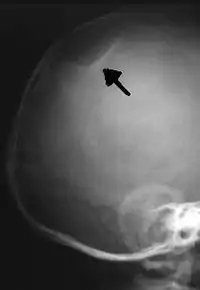

X-ray image of a depressed skull fracture in an infant. This injury is typical of child abuse cases.